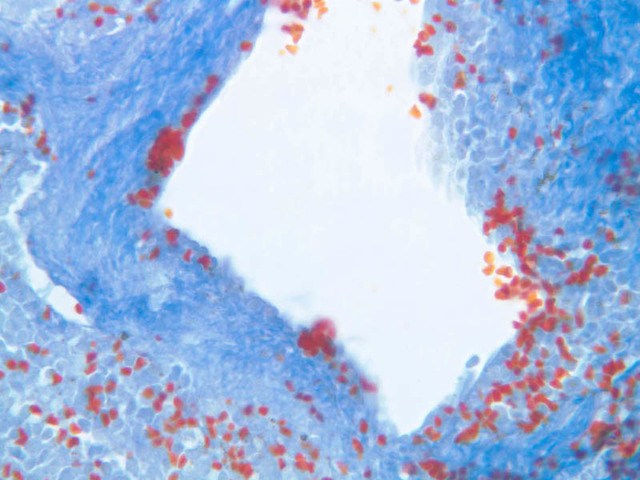

Examine the composition of the red pulp tissue. The three dimensional structure of the red pulp is analogous to Swiss cheese with the holes being the venous sinuses and the cheese being the parenchyma (i.e. splenic cords). On slide A-36 which is stained with Mallory's aniline blue locate examples of the splenic sinuses ([2.5x, 10x, 20x, 40x-labeled] [10x, 20x, 40x]). The walls of the splenic sinuses consist of adjoining specialized endothelial cells whose nuclei in many cases stand out from the wall in a bead-like fashion. The basement membrane of the epithelial cells stains blue revealing the sinuses quite nicely. Usually the sinus lumen is filled with red cells and leukocytes. The skeletal framework of the cords is provided by a network of reticular fibers. As above, the reticular cells are best seen using a reticular fiber stain (slide A-37 [2.5x, 10x, 20x, 40x-labeled]). Look for the large pale nuclei of reticular cells that have darkly stained reticular fibers. Fibers run irregularly in the cords, but clearly outline the sinuses around which they are wrapped. Notice on this same slide that there is much less reticular tissue in the white pulp than the red. The splenic cords occur around the sinuses and are distinguished by the presence of disintegrating red blood cells undergoing phagocytosis.

Here's a little histopathology: Observe slide A-40 (H&E [2.5x, 10x, 20x, 40x]). In this slide the corpses of red blood cells appear brown and can be seen littered throughout. These residual RBCs are referred to as hemosiderin. Slide A-39 (H&E [2.5x, 10x, 20x, 40x]) was prepared from a patient undergoing chemotherapy. How does the white pulp in this slide differ from the normal spleen, slide A-38?